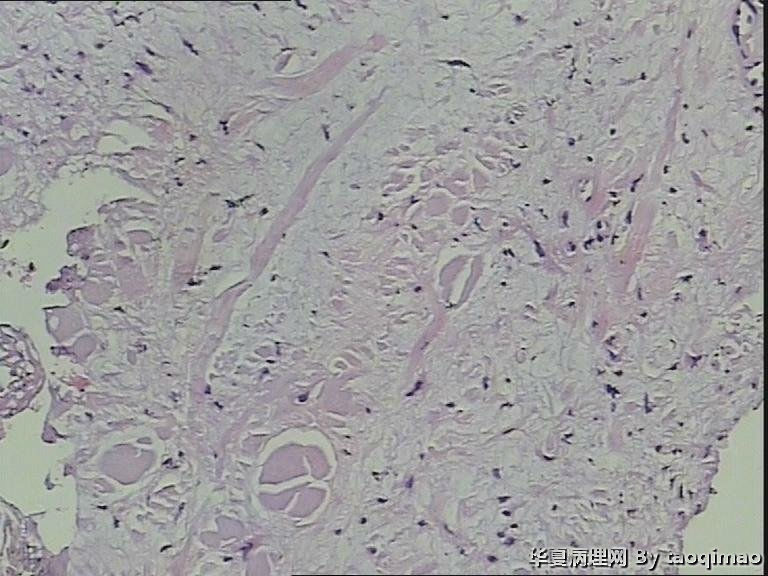

胸壁肿物

结节性筋膜炎+神经节样细胞+肌肉浸润=增生性肌炎。

粗略看了下,对软组织病变不是很在行,初步印象是增生性肌炎,几个图像里小血管内皮肿胀,周围炎细胞浸润,结合临床除外血管炎或者自身免疫相关疾病。

男,54岁,右侧胸壁肿物发现1月余,取材:灰白色不规则组织一块2*1.7*0.5cm,剖面实性灰白色,质韧。